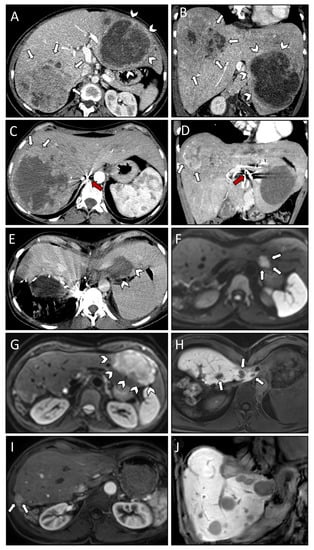

| Case Number | #1 | #2 | #3 |

|---|---|---|---|

| Patient age at diagnosis (years) | 67 | 39 | 65 |

| Patient sex | Female | Female | Female |

| Comorbidities/Notes | Parkinson’s disease | Childbed | Depression |

| WHO grade | II | II | II |

| Mitosis/10 HPF | 0 | 2 | 2 |

| Ki-67 index | 5% | 10–15% | 2% |

| Liver metastasis | |||

| Time to occurrence from initial diagnosis (years) | 8 | 8 | 15 |

| Location at initial diagnosis | Right lobe | Bilobar | Bilobar |

| Number at initial diagnosis | 1 | 3 | 3 |

| Size of largest metastasis at initial diagnosis | 13 cm | 12 cm | 13 cm |

| Paraneoplastic syndromes | Hypercalcemia | Hypoglycemia | None |

| Case #1 | Treatment | Comments | Liver Segments | Classification | Complications |

| 05.11.2018 | SRFA | 1 lesion, 13 cm, 6 needles, 47 min ablation time | V, VII, VIII | Initial | none |

| 29.11.2018 | SRFA | 1 lesion, 13 cm, 28 needles, 223 min ablation time | VIII | Initial | none |

| 11.12.2018 | SRFA | 1 lesion, 13 cm, 13 needles, 60 min ablation time | V, VII, VIII | Initial | none |

| 28.01.2019 | SRFA | 1 lesion, 13 cm, 15 needles, 43 min ablation time | V, VII, VIII | Initial | none |

| 01.03.2019 | SRFA | 1 lesion, 13 cm, 5 needles, 17 min ablation time | VIII | Local recurrence | none |

| 05.11.2020 | SRFA | 1 lesion, 13 cm, 12 needles, 59 min ablation time | VIII, V | Distant recurrence | none |